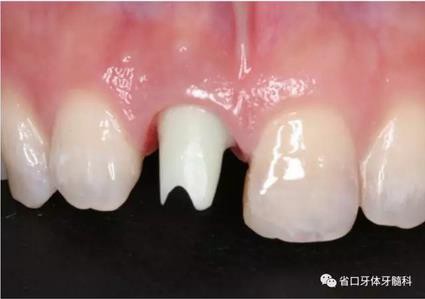

(2)制備臨時(shí)冠:術(shù)后當(dāng)天取模轉(zhuǎn)移,送工廠以Zimmer®多功能 攜帶體為臨時(shí)基臺(tái)制備臨時(shí)修復(fù),獲得舌隆突開孔螺絲固位的烤塑臨時(shí) 冠。將其就位于口內(nèi)種植體,調(diào)整正中、前伸及側(cè)方咬合無接觸,加力 10~15N·cm,可見即刻修復(fù)體良好地支持齦緣及牙齦乳頭結(jié)構(gòu)。

圖21 烤塑臨時(shí)冠

圖22 臨時(shí)冠就位前袖口檢查

圖23 就位臨時(shí)冠

圖24 臨時(shí)冠咬合調(diào)整